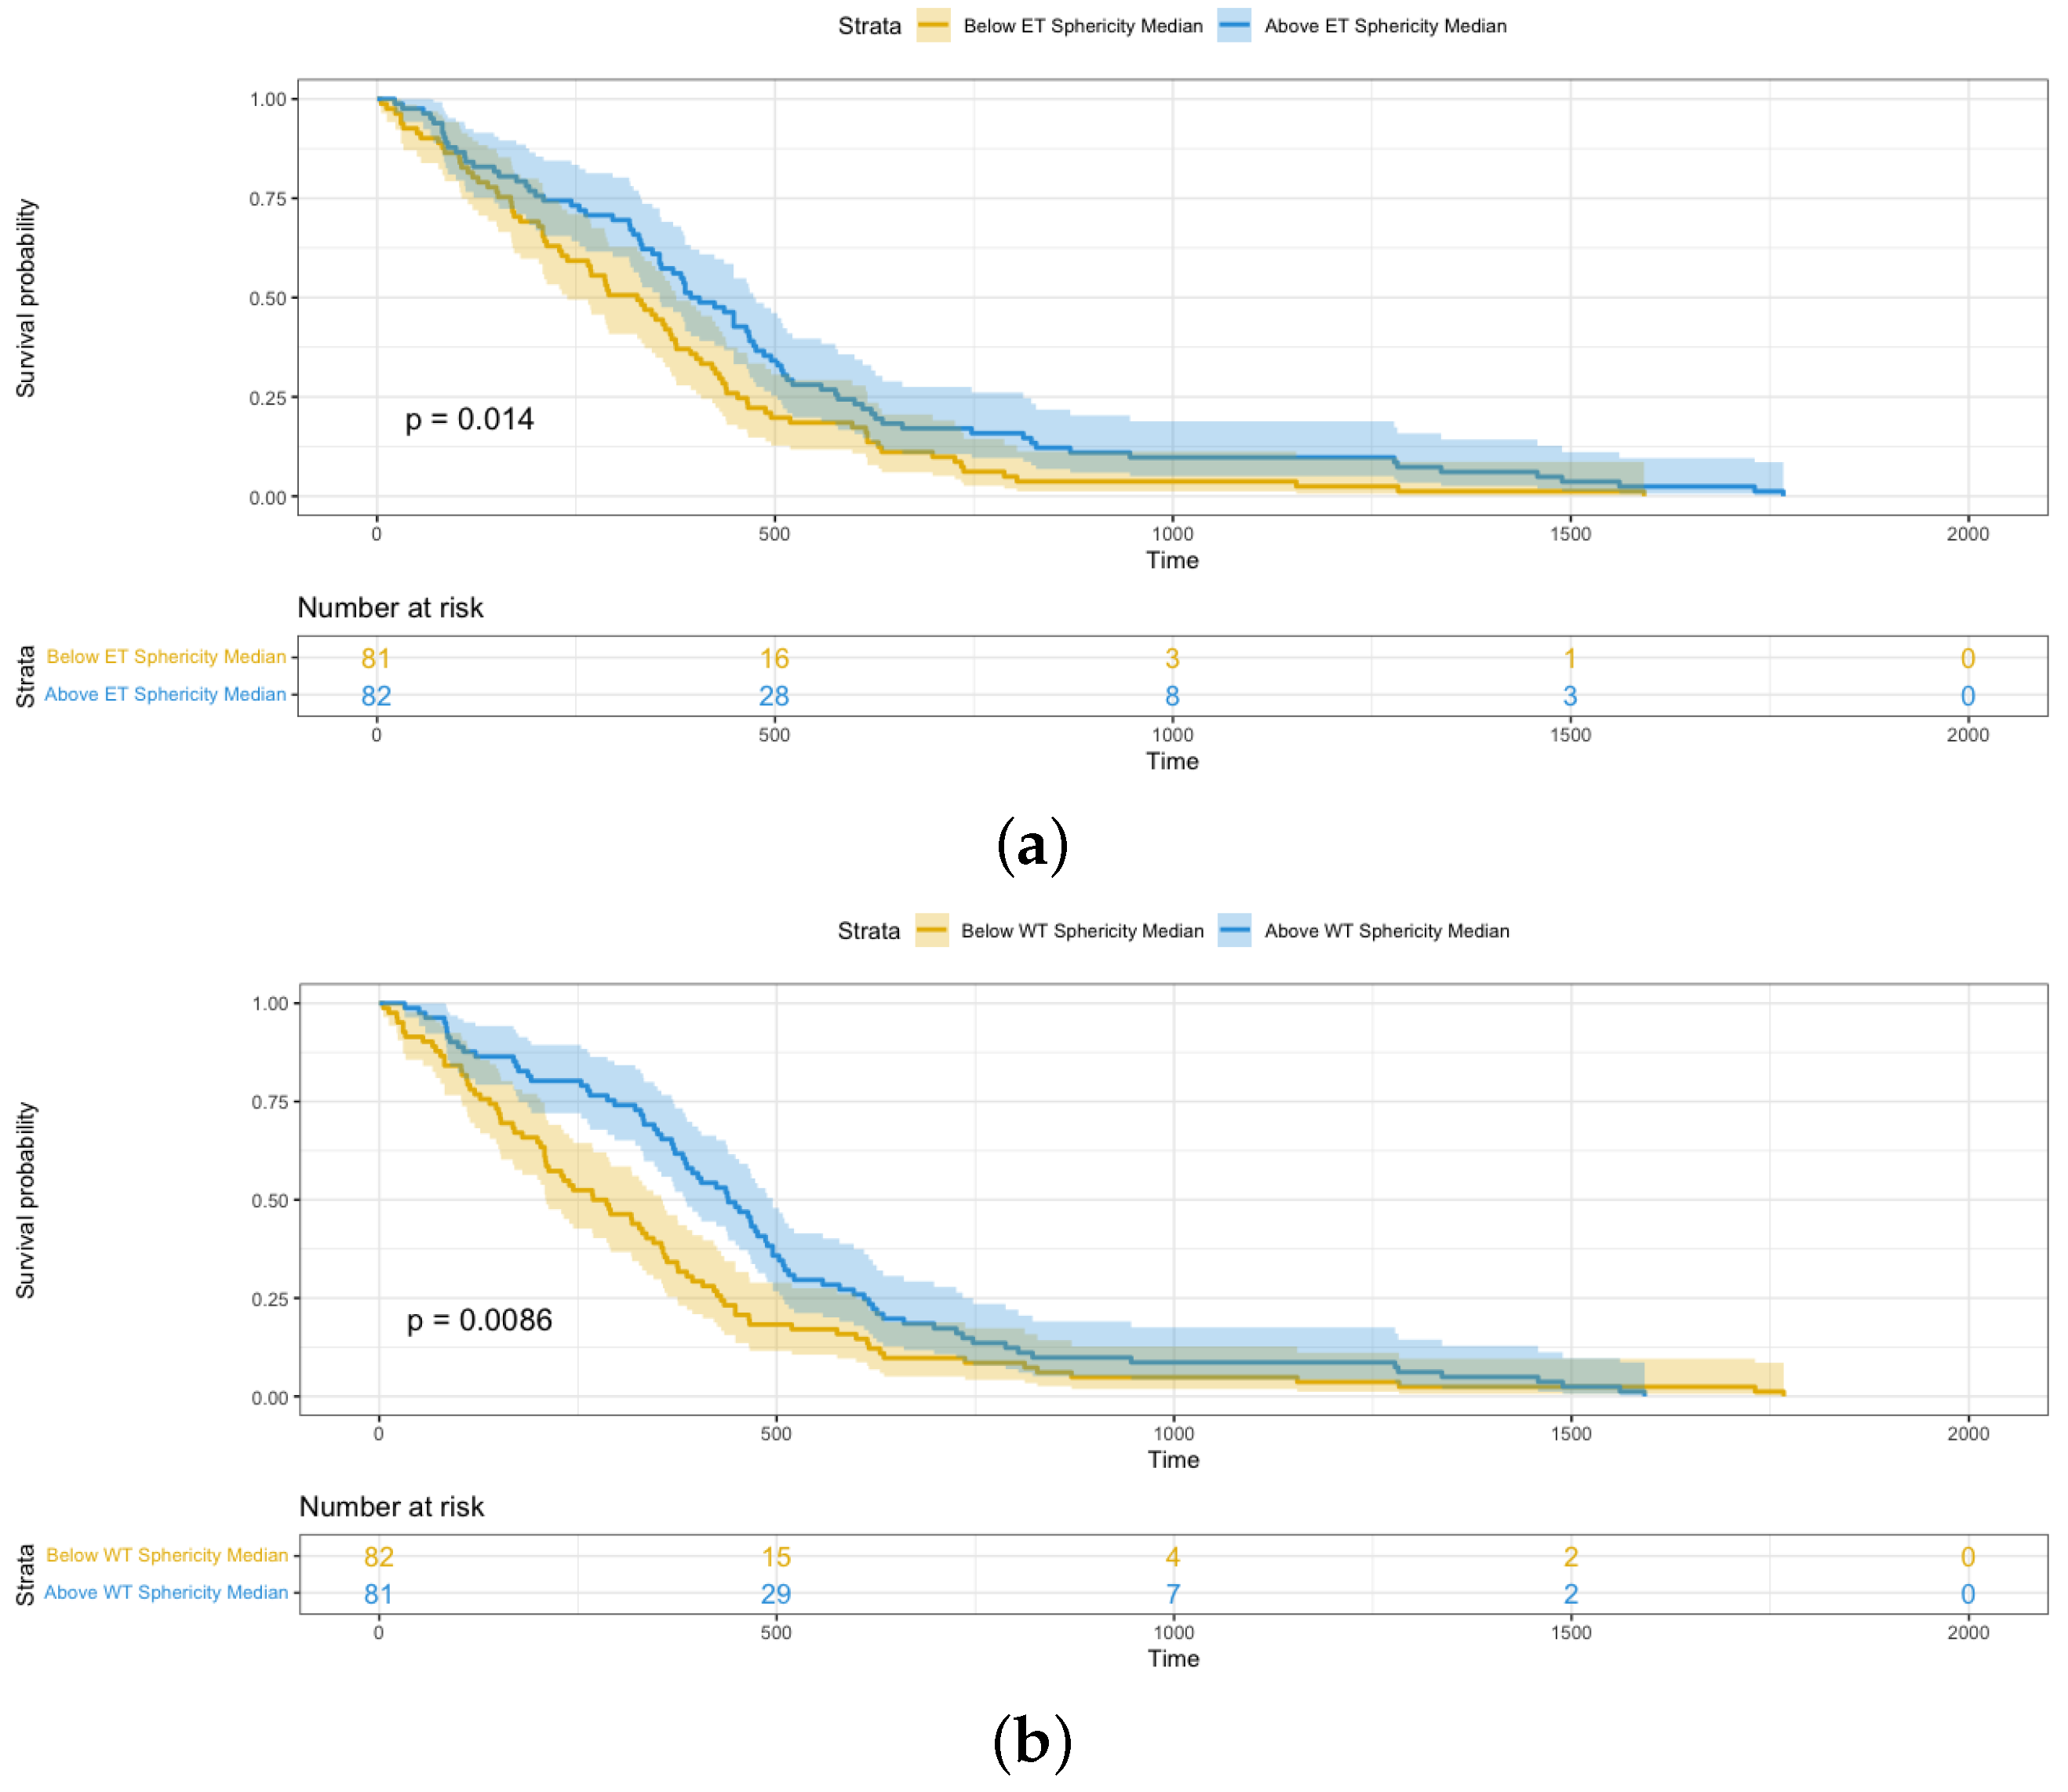

4.3. Shape Radiomics Features Analysis

| HR | 95% CI | p-Value | |

| Sphericity | 0.184 | 0.049–0.698 | 0.01 |

| Sphericity | 0.2669 | 0.069–0.762 | 0.02 |